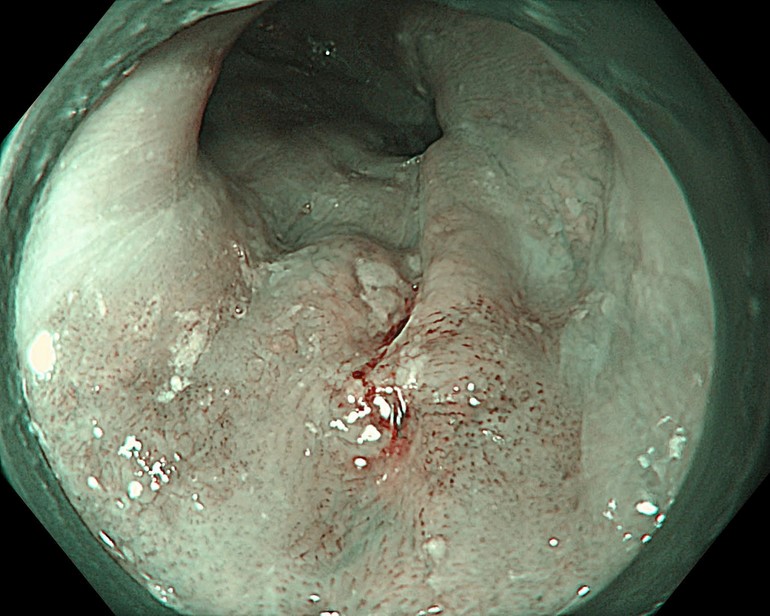

Bệnh viện K cơ sở Quán Sứ vừa trang bị 8 hệ thống máy nội soi mới, trong đó nổi bật là Olympus EVIS X1 hiện đại nhất hiện nay đi kèm với các dây XZ1200 và EZ1500 cho chức năng nhuộm màu ảo cùng phóng đại hình ảnh quang học tới 150 lần giúp chẩn đoán chính xác tổn thương ung thư và can thiệp các tổn thương một cách chính xác.

Hệ thống nội soi hiện đại được ứng dụng trong tầm soát phát hiện sớm, chẩn đoán ung thư đường tiêu hóa.

Các bác sĩ Bệnh viện K sử dụng hệ thống máy nội soi nhuộm màu phóng đại Olympus EVIS X1 hiện đại giúp hình ảnh sắc nét, hiển thị rõ tổn thương dù là nhỏ nhất, có chức năng nhuộm màu bằng ánh sáng và phóng đại lên đến 150 lần, giúp phân tích rõ ràng vi cấu trúc và vi mạch máu của tổn thương, đưa ra nhận định chính xác về tính chất tế bào học của tổn thương, phân biệt tổn thương ung thư và không ung thư từ đó đưa ra hướng can thiệp kịp thời cho người bệnh.

Mới đây, một bệnh nhân nam 63 tuổi, tiền sử hút thuốc lá nhiều năm khi nhập viện đã được chỉ định nội soi tiêu hóa trên trong chương trình khám sức khỏe định kỳ. Quá trình tầm soát ung thư vùng họng-thực quản được thực hiện bằng công nghệ NBI ngay từ khoang miệng, hạ họng-thanh quản đến toàn bộ thực quản. Nội soi phóng đại với hệ thống Olympus X1 và dây soi EZ1500 cho phép quan sát rõ vi mạch bề mặt đã phát hiện tổn thương gợi ý ung thư biểu mô vảy thực quản giai đoạn sớm ở lớp niêm mạc, có chỉ định điều trị bằng cắt tách dưới niêm mạc qua nội soi (ESD). Đây là phương pháp can thiệp tối thiểu, nhằm hạn chế xâm lấn, giúp tiết kiệm chi phí, đồng thời cải thiện thời gian sống và chất lượng cuộc sống của người bệnh. Sau can thiệp ESD, bệnh nhân hồi phục tốt và xuất viện sau 2 ngày.

Một bệnh nhân nam 67 tuổi, tiền sử nghiện rượu và hút thuốc lá khi sử dụng hệ thống nội soi Olympus EVIS X1 với công nghệ NBI phát hiện một tổn thương kích thước khoảng 10mm tại thực quản. Dựa trên hình ảnh nội soi và kinh nghiệm chuyên môn trong đánh giá ung thư sớm, các bác sĩ xác định tổn thương đã vượt quá chỉ định điều trị qua nội soi và được khuyến cáo phẫu thuật. Sau phẫu thuật, kết quả mô bệnh học xác định ung thư biểu mô thực quản đã xâm lấn vào lớp dưới niêm mạc, không phù hợp với các phương pháp can thiệp nội soi.

Trường hợp này cho thấy vai trò quan trọng của nội soi công nghệ cao kết hợp với kinh nghiệm lâm sàng trong việc đánh giá chính xác giai đoạn bệnh, từ đó lựa chọn phương pháp điều trị phù hợp, tối ưu hiệu quả và tránh các can thiệp không cần thiết.

Hình ảnh thực quản tổn thương được phát hiện qua hệ thống nội soi thế hệ mới.